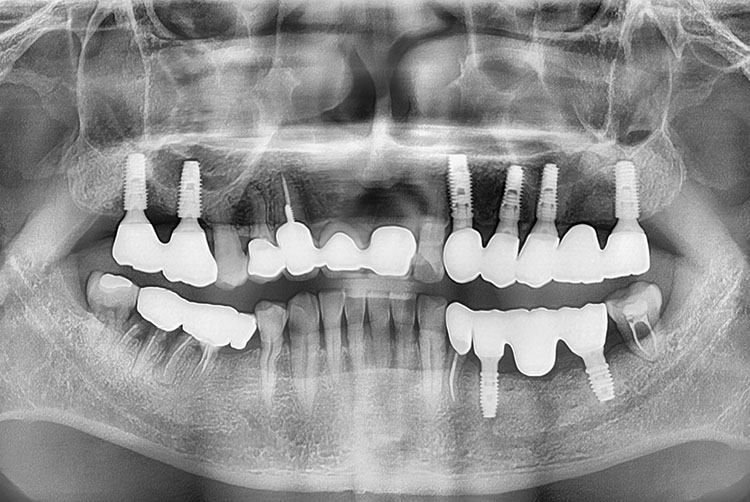

[임플란트] 임플란트

치료전 : 2015-06-30

세종치과는 많은 환자와 다양한 케이스를 바탕으로 항상 편안한 임플란트 수술을 제공하고자 노력하고,

오래동안 튼튼히 쓸 수 있는 임플란트 수술을 가장 큰 목표로 삼고 있습니다.